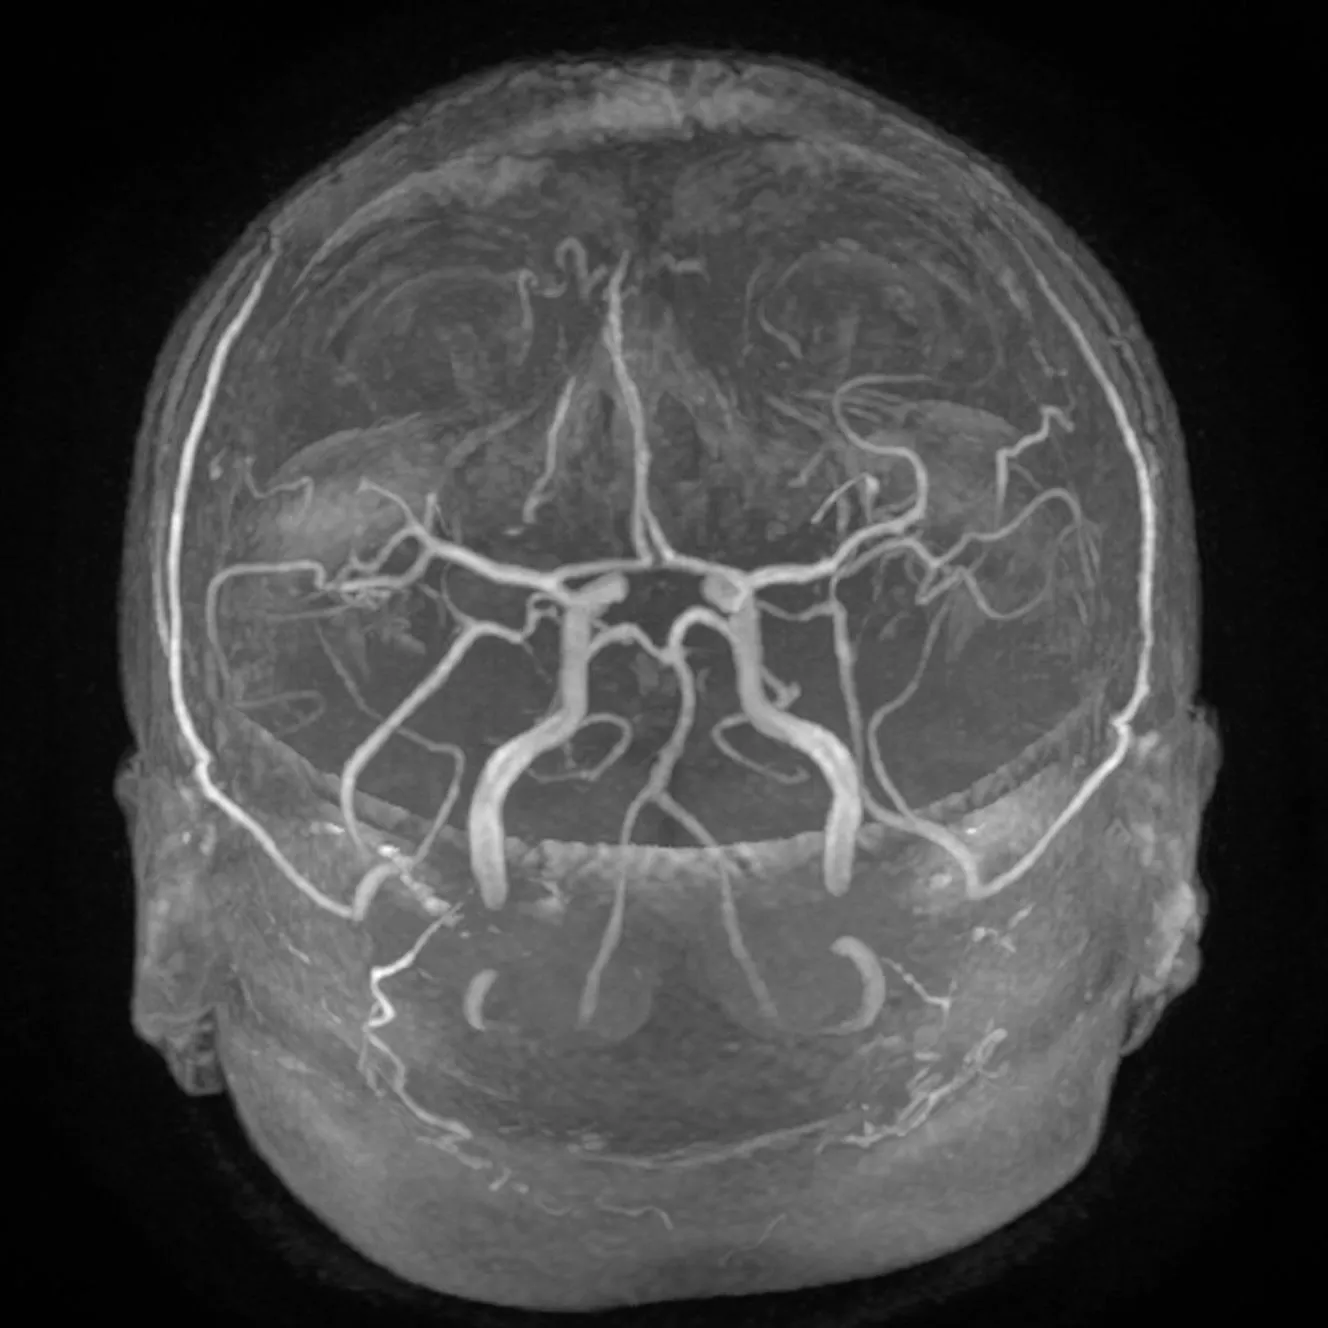

MRA MIP

MRA Oblik MIP

MRA VR